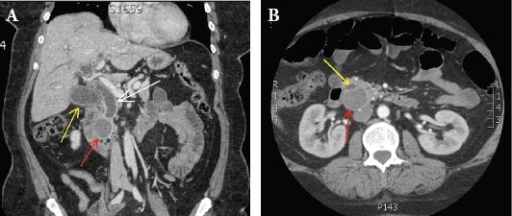

What's the Diagnosis?